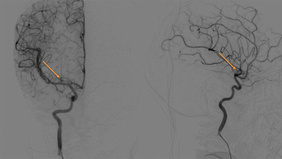

Tandem Stenosis & Extracranial Carotid Rescue Stenting

By Muralidharan VETRIVEL

Published on December 11, 2025